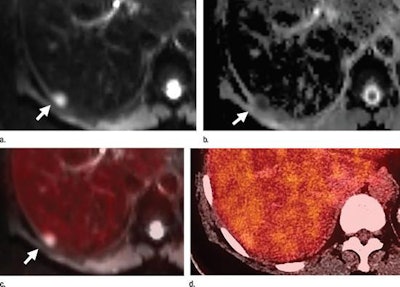

In detecting distant metastases in the liver, PET/MRI had greater sensitivity than PET/CT. The researchers credited DWI-MRI in finding up to 40 liver metastases, compared with 28 liver metastases with PET/CT.

PET/MRI also achieved greater detection of bone lesions, with a combined 207 lesions for both readers, compared with a total of 196 lesions with PET/CT for both readers. In the comparison of lung metastases, both readers tallied a total of 55 true-positive results with PET/CT, compared with 37 true-positive findings with PET/MRI.

Axial PET/MRI (a-c) and PET/CT (d) images are from a 64-year-old woman with a history of left breast cancer metastatic to lung and bone. Images were obtained to monitor response during chemotherapy. A liver metastasis (arrow) is seen on PET/MRI (a-c), but not on PET/CT (d). The metastasis is best seen on the diffusion-weighted MR image (a), with corresponding low signal intensity on the apparent diffusion coefficient map (b). There is minimal corresponding FDG uptake on the fused diffusion-weighted and PET image (c). The metastasis is not seen on PET/CT images (d). Images courtesy of Radiology.In addition, the readers found 15 and 14 brain metastases, respectively, in five (10%) of the 51 subjects with PET/MRI. PET/CT found no brain metastases. The number of brain metastases came as a surprise to Melsaether and colleagues.